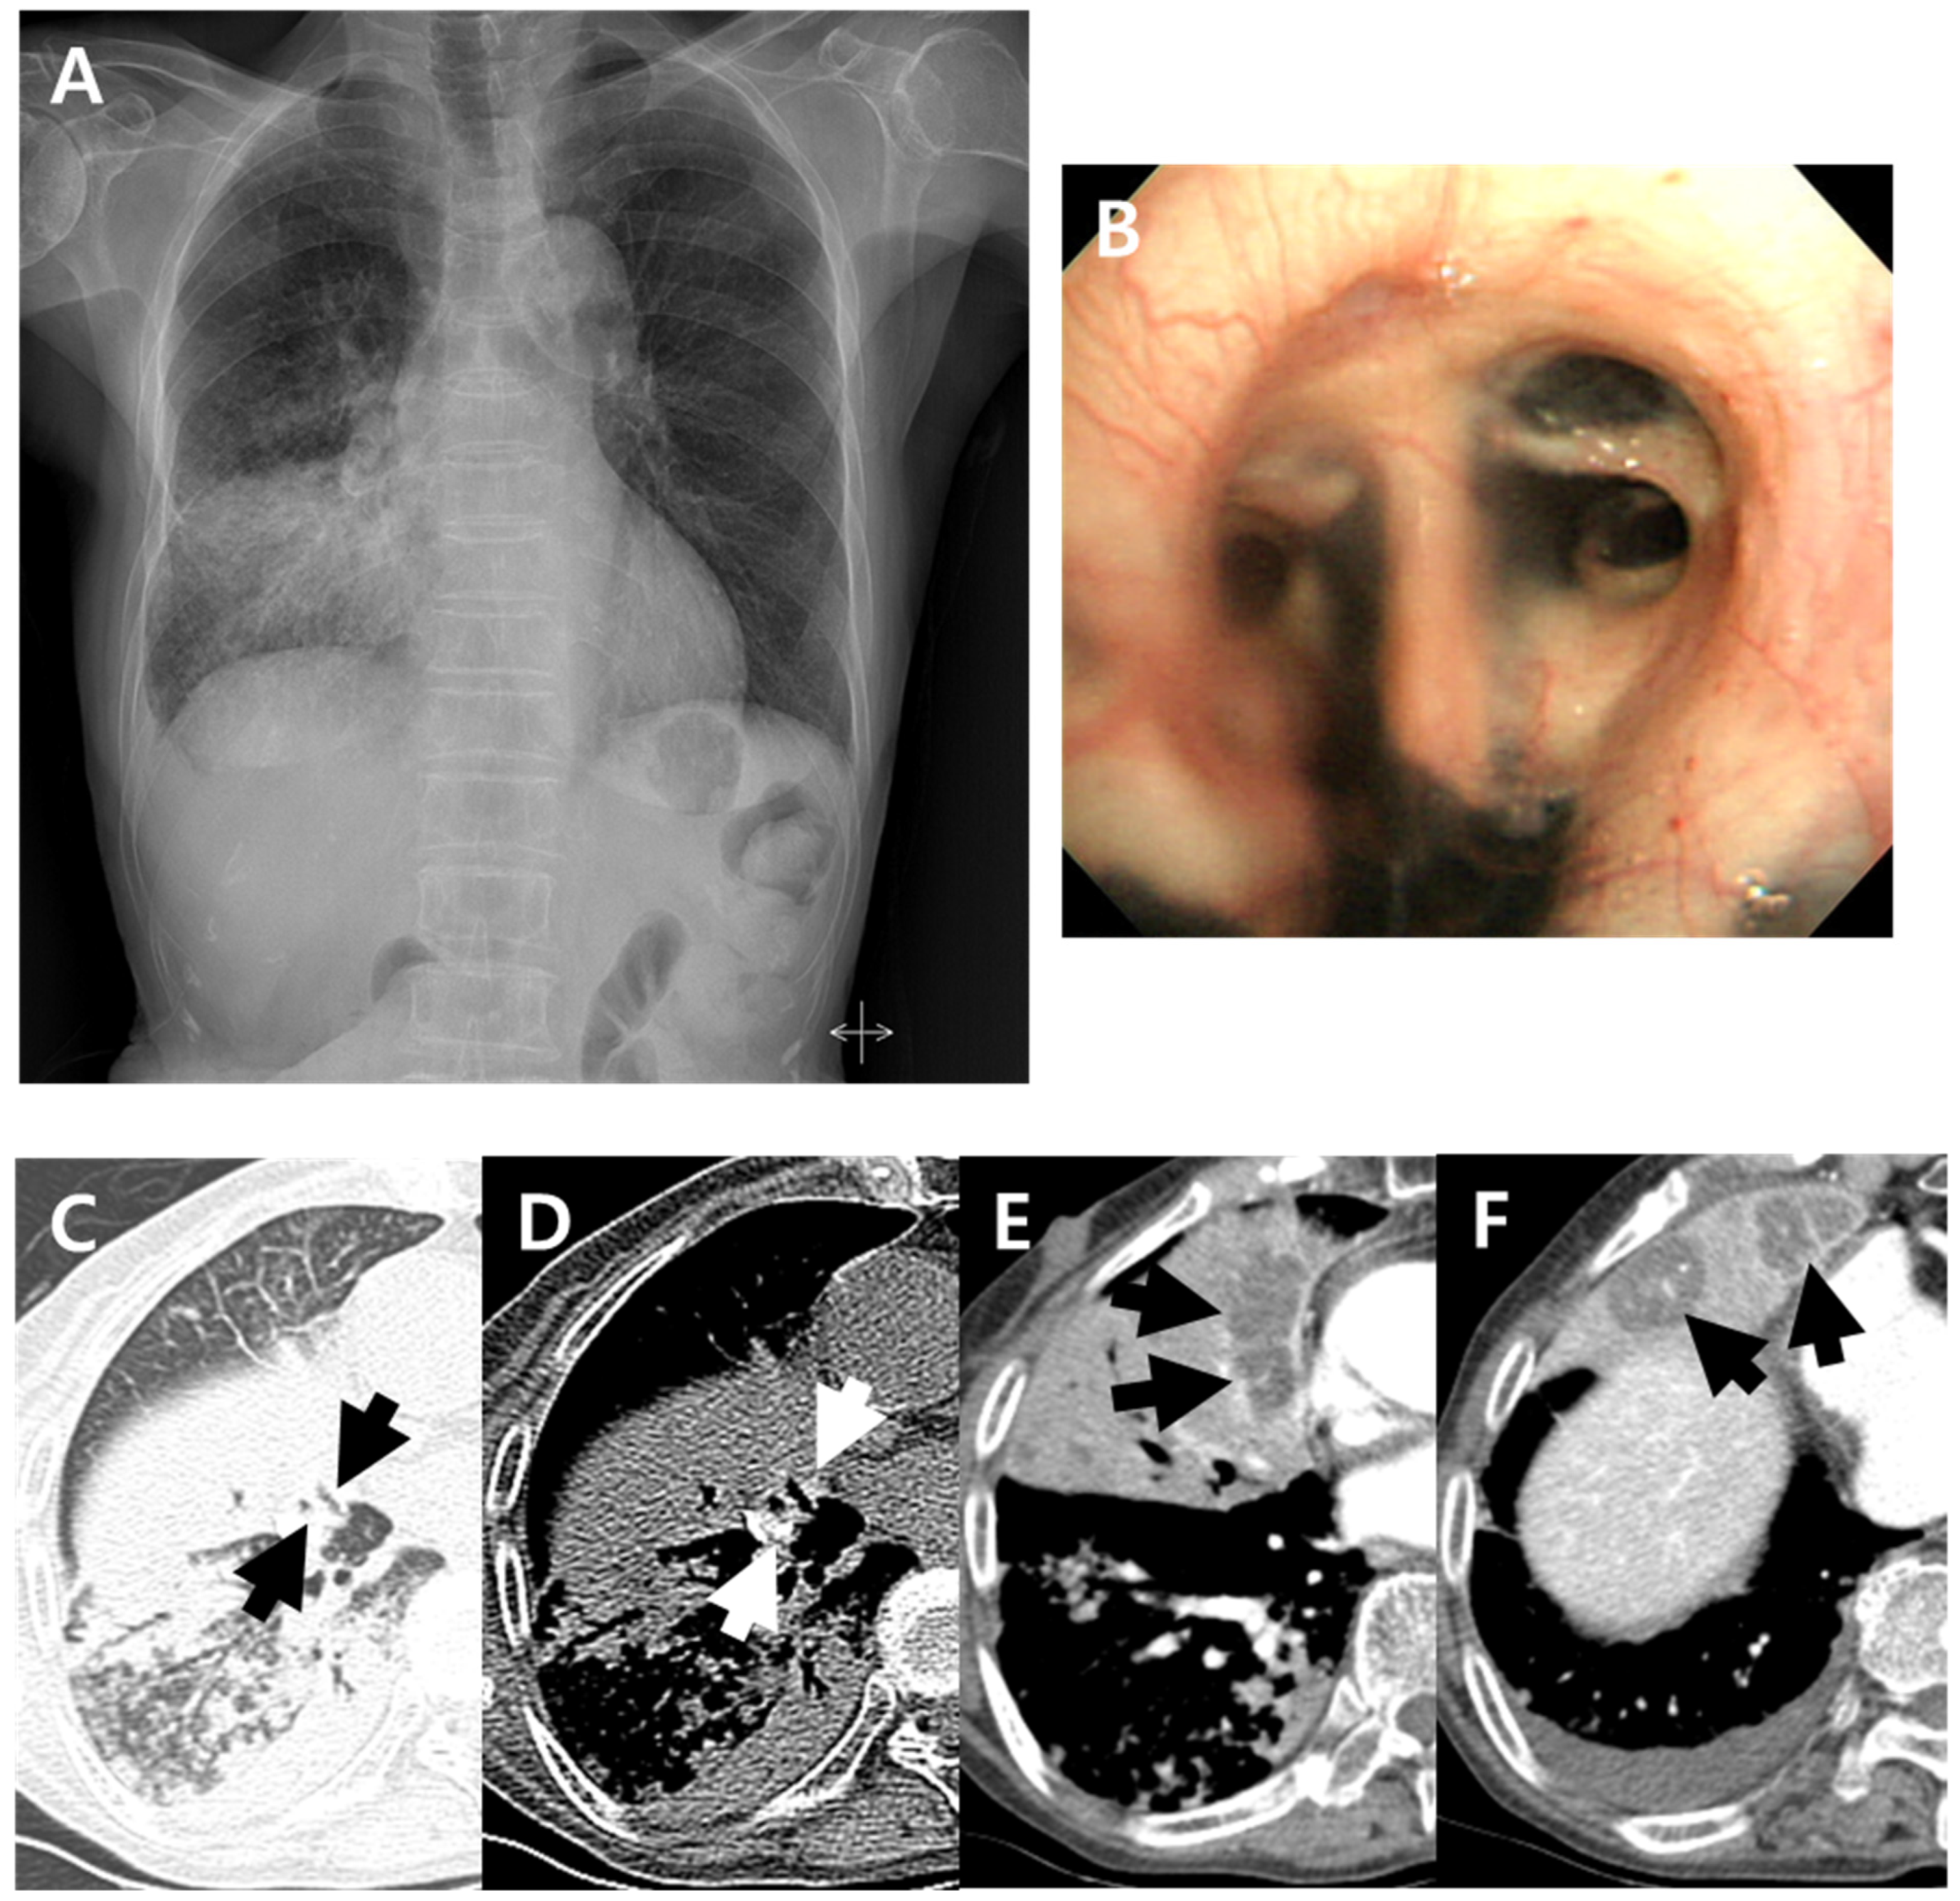

Figure 1.

A 79-year-old woman with pulmonary tuberculosis and underlying bronchial anthracofibrosis presented with an abnormal chest plain radiograph. (A) Chest plain radiograph showed consolidation and ill-defined nodular opacities in right lower lung field with lower lobe predominance. (B) Bronchoscopic image showed luminal narrowing at segmental bronchi of right middle lobe with multifocal deposition of black pigmentation, and bronchial anthracofibrosis was diagnosed. (C,D) Non-enhanced axial CT scan showed bronchostenosis (black arrows) at medial and lateral segmental bronchi of right middle lobe and peribronchial hyperattenuation (white arrows) around medial and lateral segmental bronchi of right middle lobe. These CT findings suggested bronchial anthracofibrosis. (E,F) Contrast-enhanced axial CT scan showed internal low-density areas (arrows) within atelectasis of right middle lobe. These findings were atypical CT findings of pulmonary tuberculosis, which cannot be suspected of TB. By the way, clustered micronodules with tree-in-buds and consolidations in right lower lobe were shown on the axial CT scan which were well known typical CT findings of pulmonary tuberculosis. CT = computed tomography.